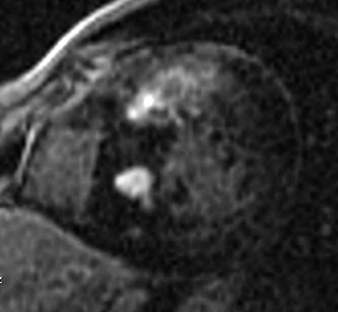

Fig.: 6., 7., 8.: MRI: Extended myocardial infarct of the inferior ventricular wall Late phase contrast enhancement in the thin inferior wall of the ventricle in cross sectional and longitudinal images, MRI